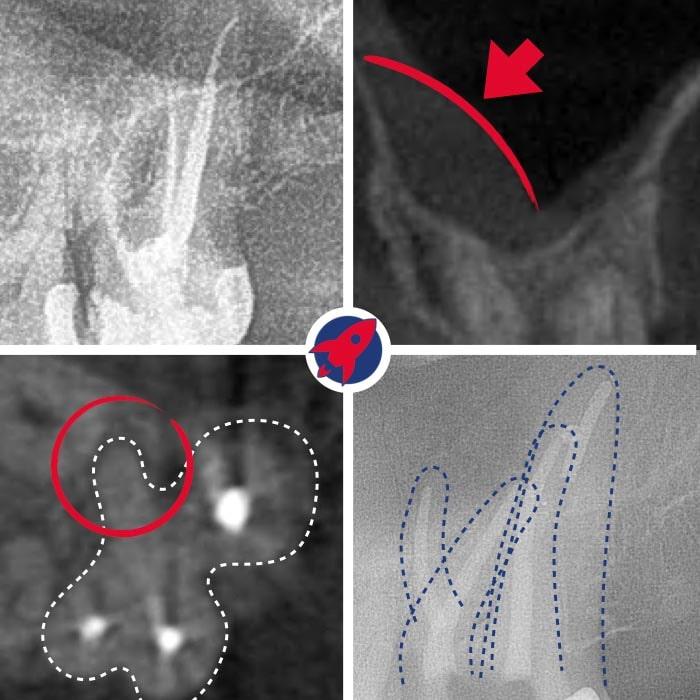

Treatment Under the Dental Microscope

The core of our endodontics. The up to 25x magnification enables the visualization of the finest canals, which are impossible to find with the naked eye.

Gentle Preparation

Instead of manual files, we use flexible, machine-driven nickel-titanium instruments that thoroughly and gently clean even severely curved canals.

Cleaning Under the Microscope

The tooth is isolated. Using the X-ray and the magnification of the microscope, the canals are opened, flushed, and cleaned and disinfected with machine-driven instruments down to the tip.